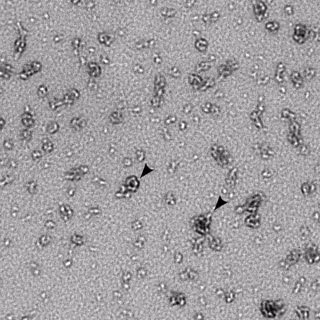

FLICKR/NIAID

'Chlamydia trachomatis' es la infección de transmisión sexual (ETS) más común en los países industrializados. Por lo general, no causa síntomas, pero puede aumentar el riesgo de infección por virus de inmunodeficiencia humana (VIH) y provocar complicaciones a largo plazo en las mujeres, como la enfermedad inflamatoria pélvica, el embarazo ectópico y la infertilidad.